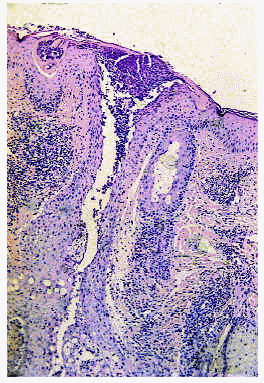

Los hallazgos del examen histológico son muy característicos. Se observa una zona ulcerada de la mucosa cubierta por una capa de exudado fibrinoide con detritus celulares (fig. 11). En la base de la úlcera hay tejido de granulación, con incremento en el número de capilares con células endoteliales prominentes. En los bordes de la úlcera el epitelio aparece hiperplásico. La submucosa está ocupada por un infiltrado difuso compuesto fundamentalmente por eosinófilos y, en cantidad variable, por linfocitos, plasmocitos e histiocitos. El infiltrado con predominio de eosinófilos llega hasta el plano muscular (fig. 12) y las fibras musculares aparecen edematosas y con alteraciones degenerativas127, 131, 134, 138. Hay autores que han descrito la presencia asociada de vasculitis leucocitoclástica138.

Fig. 11.--Úlcera eosinofílica: aspecto histológico. Cortesía de la doctora Emilia Fernández (Salamanca).

Fig. 12.--Úlcera eosinofílica: aspecto histológico. Cortesía de la doctora Emilia Fernández (Salamanca).